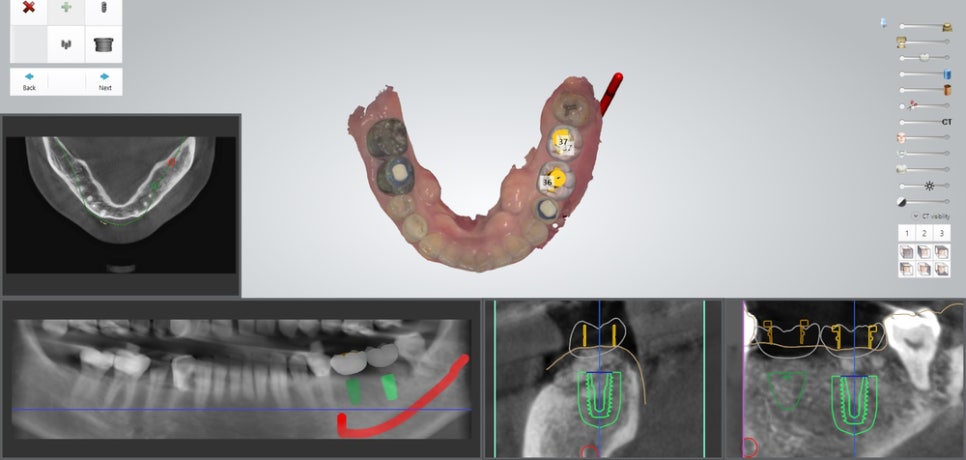

컴퓨터 분석을 통해

심어질 픽스쳐의 위치와 방향,

각도 등을 결정했습니다.

이를 통해 주변 조직과의 거리도

확실하게 알 수 있는데요.

신경관과의 거리가 어느정도 주어졌기에

안전하게 심을 수 있겠네요.